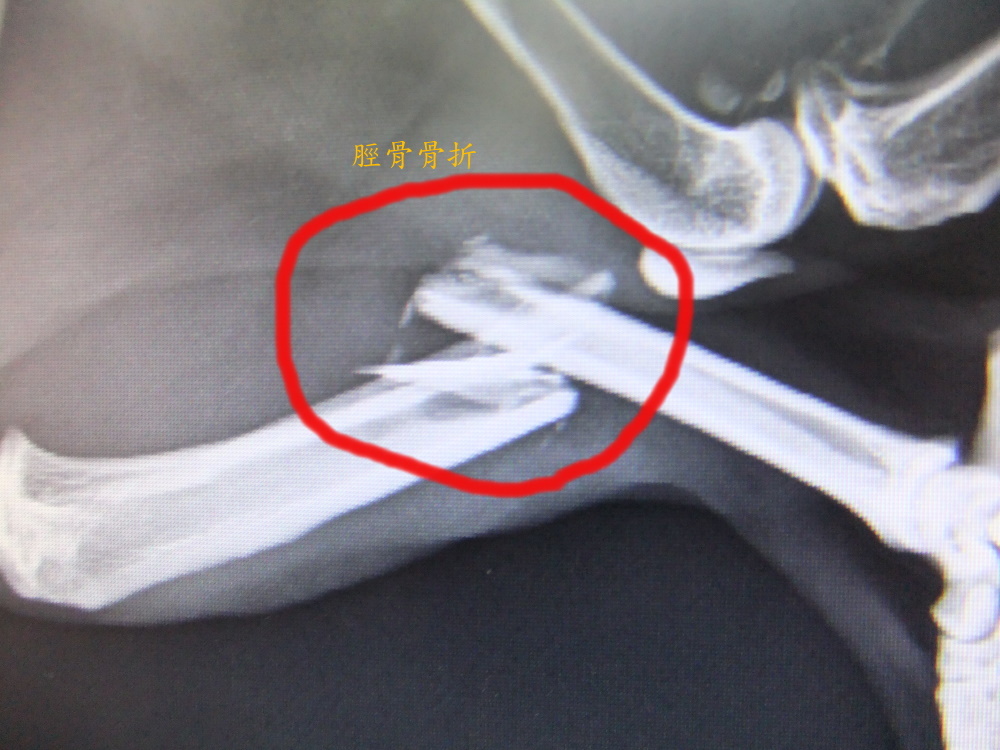

主題: 有家歸不得的乳牛骨折貓--脛骨腓骨斷裂修復手術 申請者姓名: 王惠貞 花色: 申請日期: 2012-04-27 01:20:58 申請者部落格: 申請者臉書網址: 所在縣市/合作醫院: 台北市/其他院所醫助專案(醫院請先MAIL溝通) 治療費用: 15000元 需求人數: 15人 已結案 (2012-06-21 01:13:31) 報名人員: Chi-Ju Chen(已付款)、吳家儀(已付款)、sally(已付款)、sally(已付款)、sally(已付款)、Emilia Chen(已付款)、Ku-ai Gina Chen(已付款)、philip(已付款)、GiMi Li(已付款)、波波(已付款)、張珍妮(已付款)、Hsin-Yi Chiao(已付款)、Shih Ju Chiu(已付款)、Irena(已付款)、Ny To(已付款)、 候補人員: 小舟、小舟、小舟、 動物病情說明: 這隻tnr乳牛貓生活的很坎坷,被「人」盯上,有「里」歸不得,被下令不准待在出生至長大的里,以換取其他貓咪的生活權,一年多來安置不同的志工家,逃跑了兩次,這次逃跑後沒這麼幸運,牠在連棟各大樓鐵皮屋頂上活動兩個月之久,志工頂樓隔間有放飼料及水,但4月中,在消失3天後周六晚被找到,虛脫的倒在巷子旁,經協會幫助,緊急先送最近的動物醫院,醫生驗血報告所有指數都很高,嚴重脫水,左小腿研判骨折,可能從高處掉落有三天之久沒進食喝水,先住院打點滴期盼指數恢復正常,由於醫院沒x光機、開刀台,週一轉至沐恩動物醫院治療,x光片顯示左小腿脛骨腓骨斷裂,右腿骨板根部關節處傷口深,有發炎,部分血指數有下降但肝腎指數仍高,醫生週四才能開刀打骨鈑,所以先作了骨架並住院觀察,目前術後傷口恢復不錯但食慾極差,為省醫療費自行帶回照顧,希望他能打起精神恢復以前愛吃愛叫的個性,並繼續和我們一起尋找能夠自由與幸福並存的地方,住院及開刀醫療費用兩家醫院2870+27855=30725,費用對我們來說負擔高,需15000元幫助,希望大家一起幫忙,一人1000元!剩餘醫療費及後續取出骨鈑費用我們自行負擔,以節省資金可救助其他之貓咪